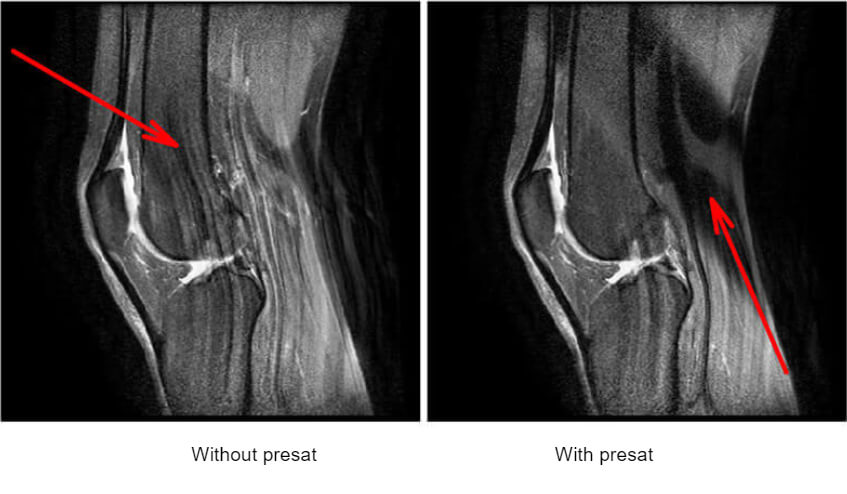

Fat Sat: Examples

This is an example of fat saturation. Fat Sats are common with extremity imaging. Removing the fat around the joint and from around and within the bone, allows us to see things that might be hidden. Additionally, it can help with diagnosis. Notice the bright signal in the humerus just below the anatomical neck. The fact we can see this on fat sat tells us that this is pathology. If it were fat within the bone it would be difficult to tell the difference between fat or pathology. We know that fat will show up bright on a T1 sequence. If we have saturated the fat, pathologies will be bright and we know they are “real”.

The fat can be removed by selective excitation based on the property that the protons of water and fat do not rotate at the same frequency.

Principle of Pre Sat

In order to saturate all the tissues in a given zone, we will use a technique similar to that of fat sat. It involves the use of a selective pulse before the sequence applied (we have chosen the simplest sequence here, the spin-echo). We apply a slice selection gradient to make the protons of a precise section resonate.

The RF wave applied covers all the rotation frequencies of the hydrogen protons of the section: all protons in the section are flipped 90° and the others are untouched. If we now apply the standard sequence. Protons inside the pre-saturation band will not have a transverse component and will thus not give a signal. These pre-saturation bands are called Sat on GE, Rest Slab on Philips or Reg. Saturation on Siemens. Example of using a saturation band to eliminate involuntary motion. The venous flow in the back of the brain is causing an artifact.